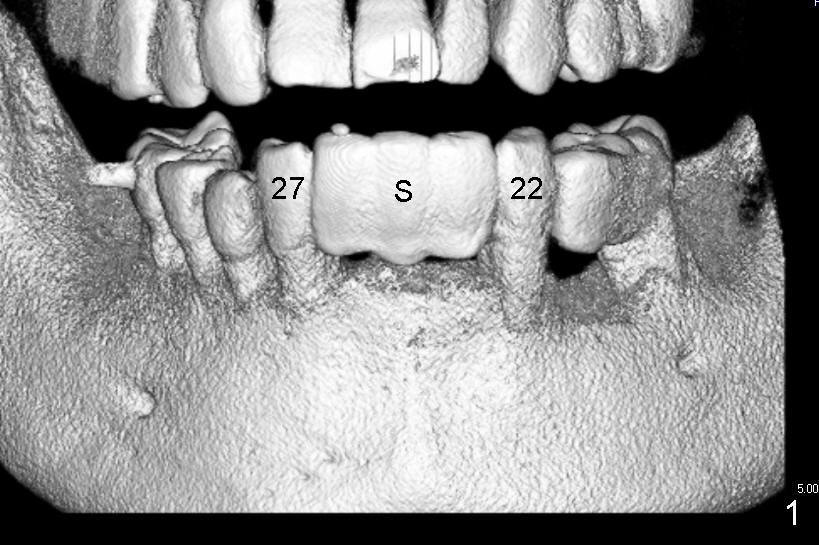

Kent has lost four of the lower incisors (Fig.1 between #22 and 27, S: stent for CT scan). It is planned to place two or three 3.0 mm one piece implants (Fig.2 axial section at root level). Intraop PA shows that one of 1.5 mm pilot drills is close to #22 (Fig.3). The trajectory of this osteotomy was then changed with difficulty; the final PA shows two of 3.0x17 mm one piece implants (Fig.4). Postop, the patient is doing fine. To get the best trajectory, we will penetrate the bone half distance of the intended length with 1.5 mm pilot drills, take PA to see how the angulation is and how close to the adjacent tooth and finish the osteotomy appropriately.